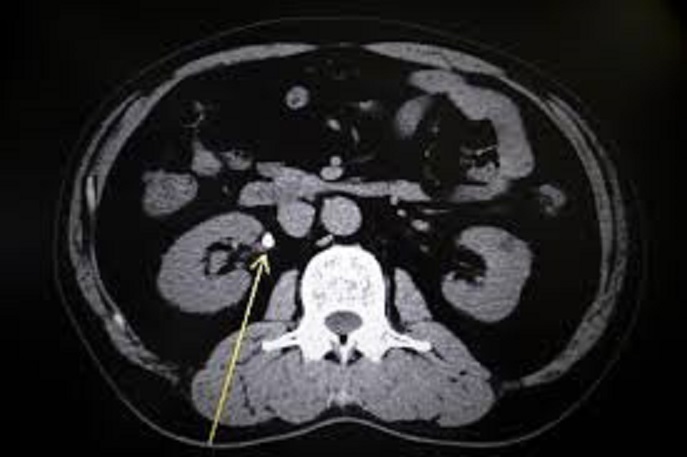

多くの場合、医師は症状や病歴に基づいて腎臓結石を診断できます。 CT スキャン(CAT スキャンとも呼ばれます) は、一連の X 線を使用して体内の画像を作成します。 CT スキャンでは、従来の X 線よりも詳細な画像が得られます。

各スキャンは、腎臓の上部から膀胱の底部までの領域をカバーできます。これらのスキャンにより、医師は結石の大きさを確認したり、腎臓から膀胱につながる尿管の異常を特定したりすることもできます。

腎臓結石を診断するための CT スキャンはどの程度正確ですか?

CT スキャンは腎臓結石を非常に正確に特定できます。